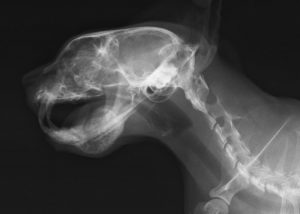

上は、当院の症例レントゲンです。(猫)

下顎に霜柱ができたような、モヤモヤした像がみえます。これは下顎の骨が崩壊した所です。